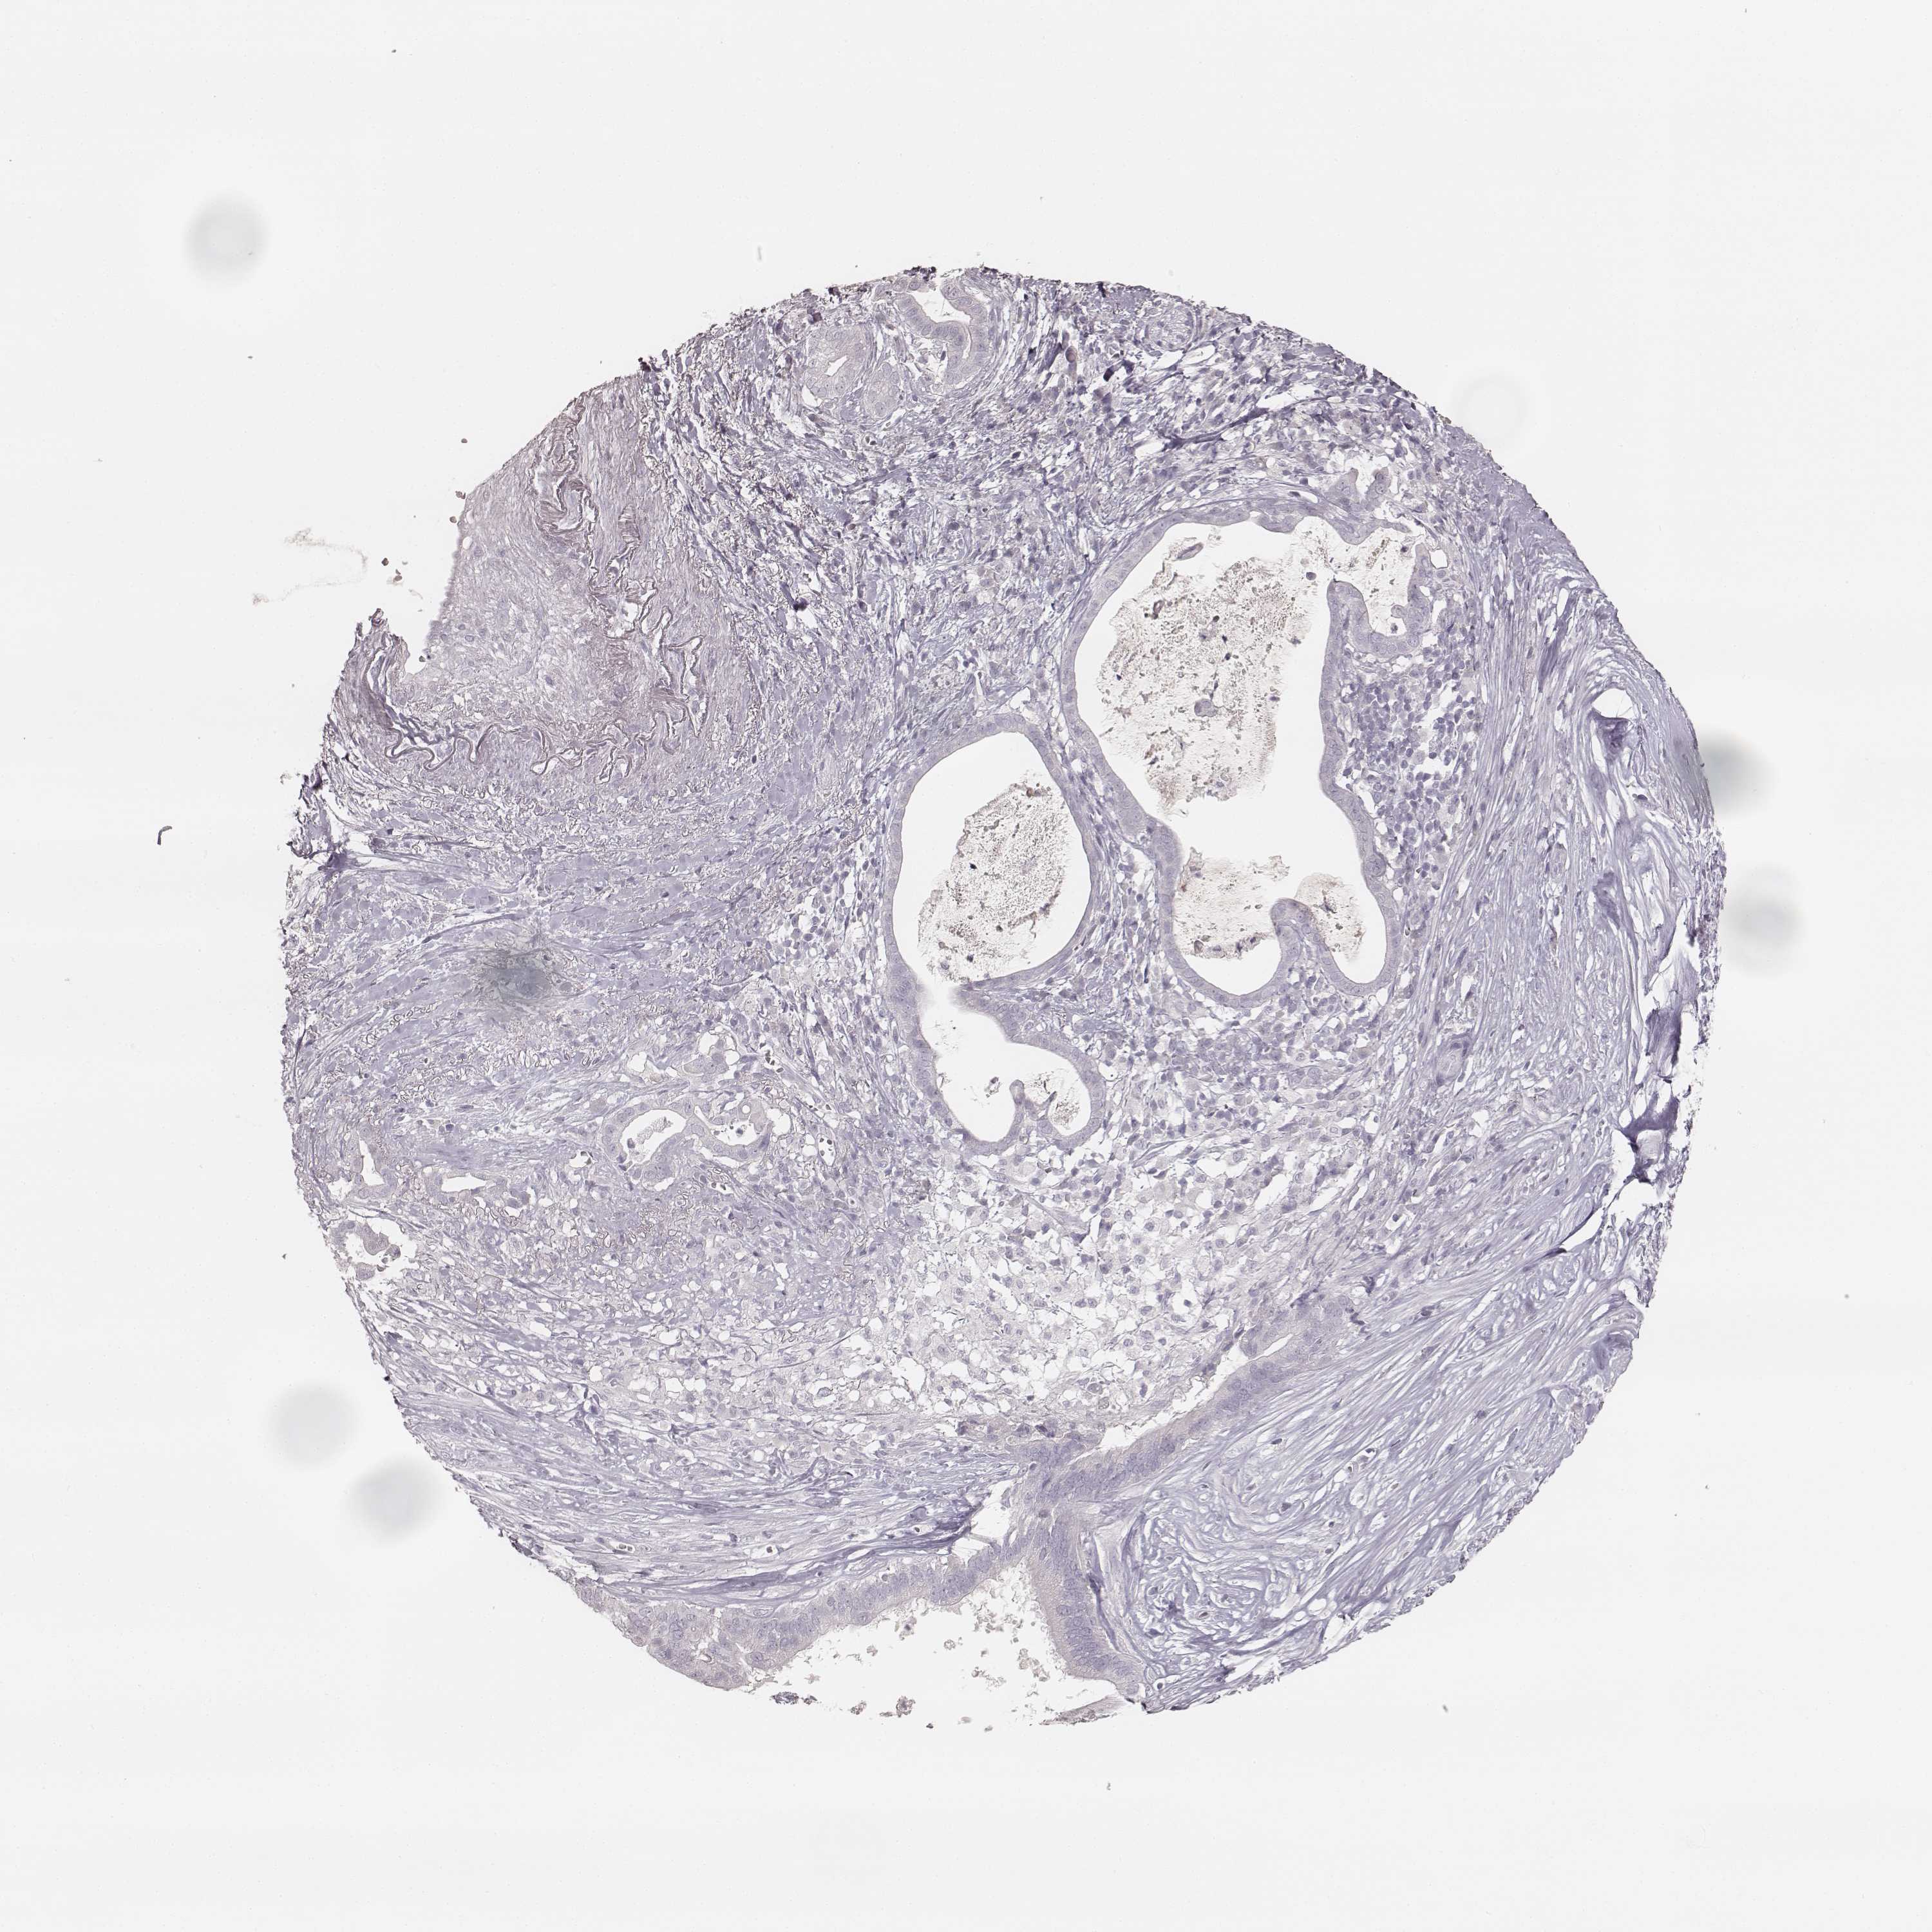

PANCREATIC CANCER - Protein expressioni

A mouse-over function shows sample information and annotation data. Click on an image to view it in a full screen mode. Samples can be filtered based on level of antibody staining by selecting one or several of the following categories: high, medium, low and not detected. The assay and annotation is described here.

Note that samples used for immunohistochemistry by the Human Protein Atlas do not correspond to samples in the TCGA dataset.

Antibody stainingi

Antibody staining in the annotated cell types in the current human tissue is reported as not detected, low, medium, or high, based on conventional immunohistochemistry profiling in selected tissues. This score is based on the combination of the staining intensity and fraction of stained cells.

Each image is clickable and will lead to virtual microscopy that enables deeper exploration of all samples and also displays staining intensity scores, fraction scores and subcellular localization as well as patient and tissue information for each sample.

Antibody HPA049550

Antibody HPA055194

Staining

High

Medium

Low

Not detected

Intensity

Strong

Moderate

Weak

Negative

Quantity

>75%

75%-25%

<25%

None

Location

Nuclear

Cytoplasmic/membranous

Cytoplasmic/membranous,nuclear

Adenocarcinoma, NOS